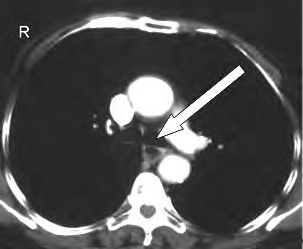

Na obrazie TK zaznaczono zatokę

Ilustracja do pytania 16

A. czołową w przekroju czołowym.

B. czołową w przekroju strzałkowym.

C. szczękową w przekroju strzałkowym.

D. szczękową w przekroju czołowym.